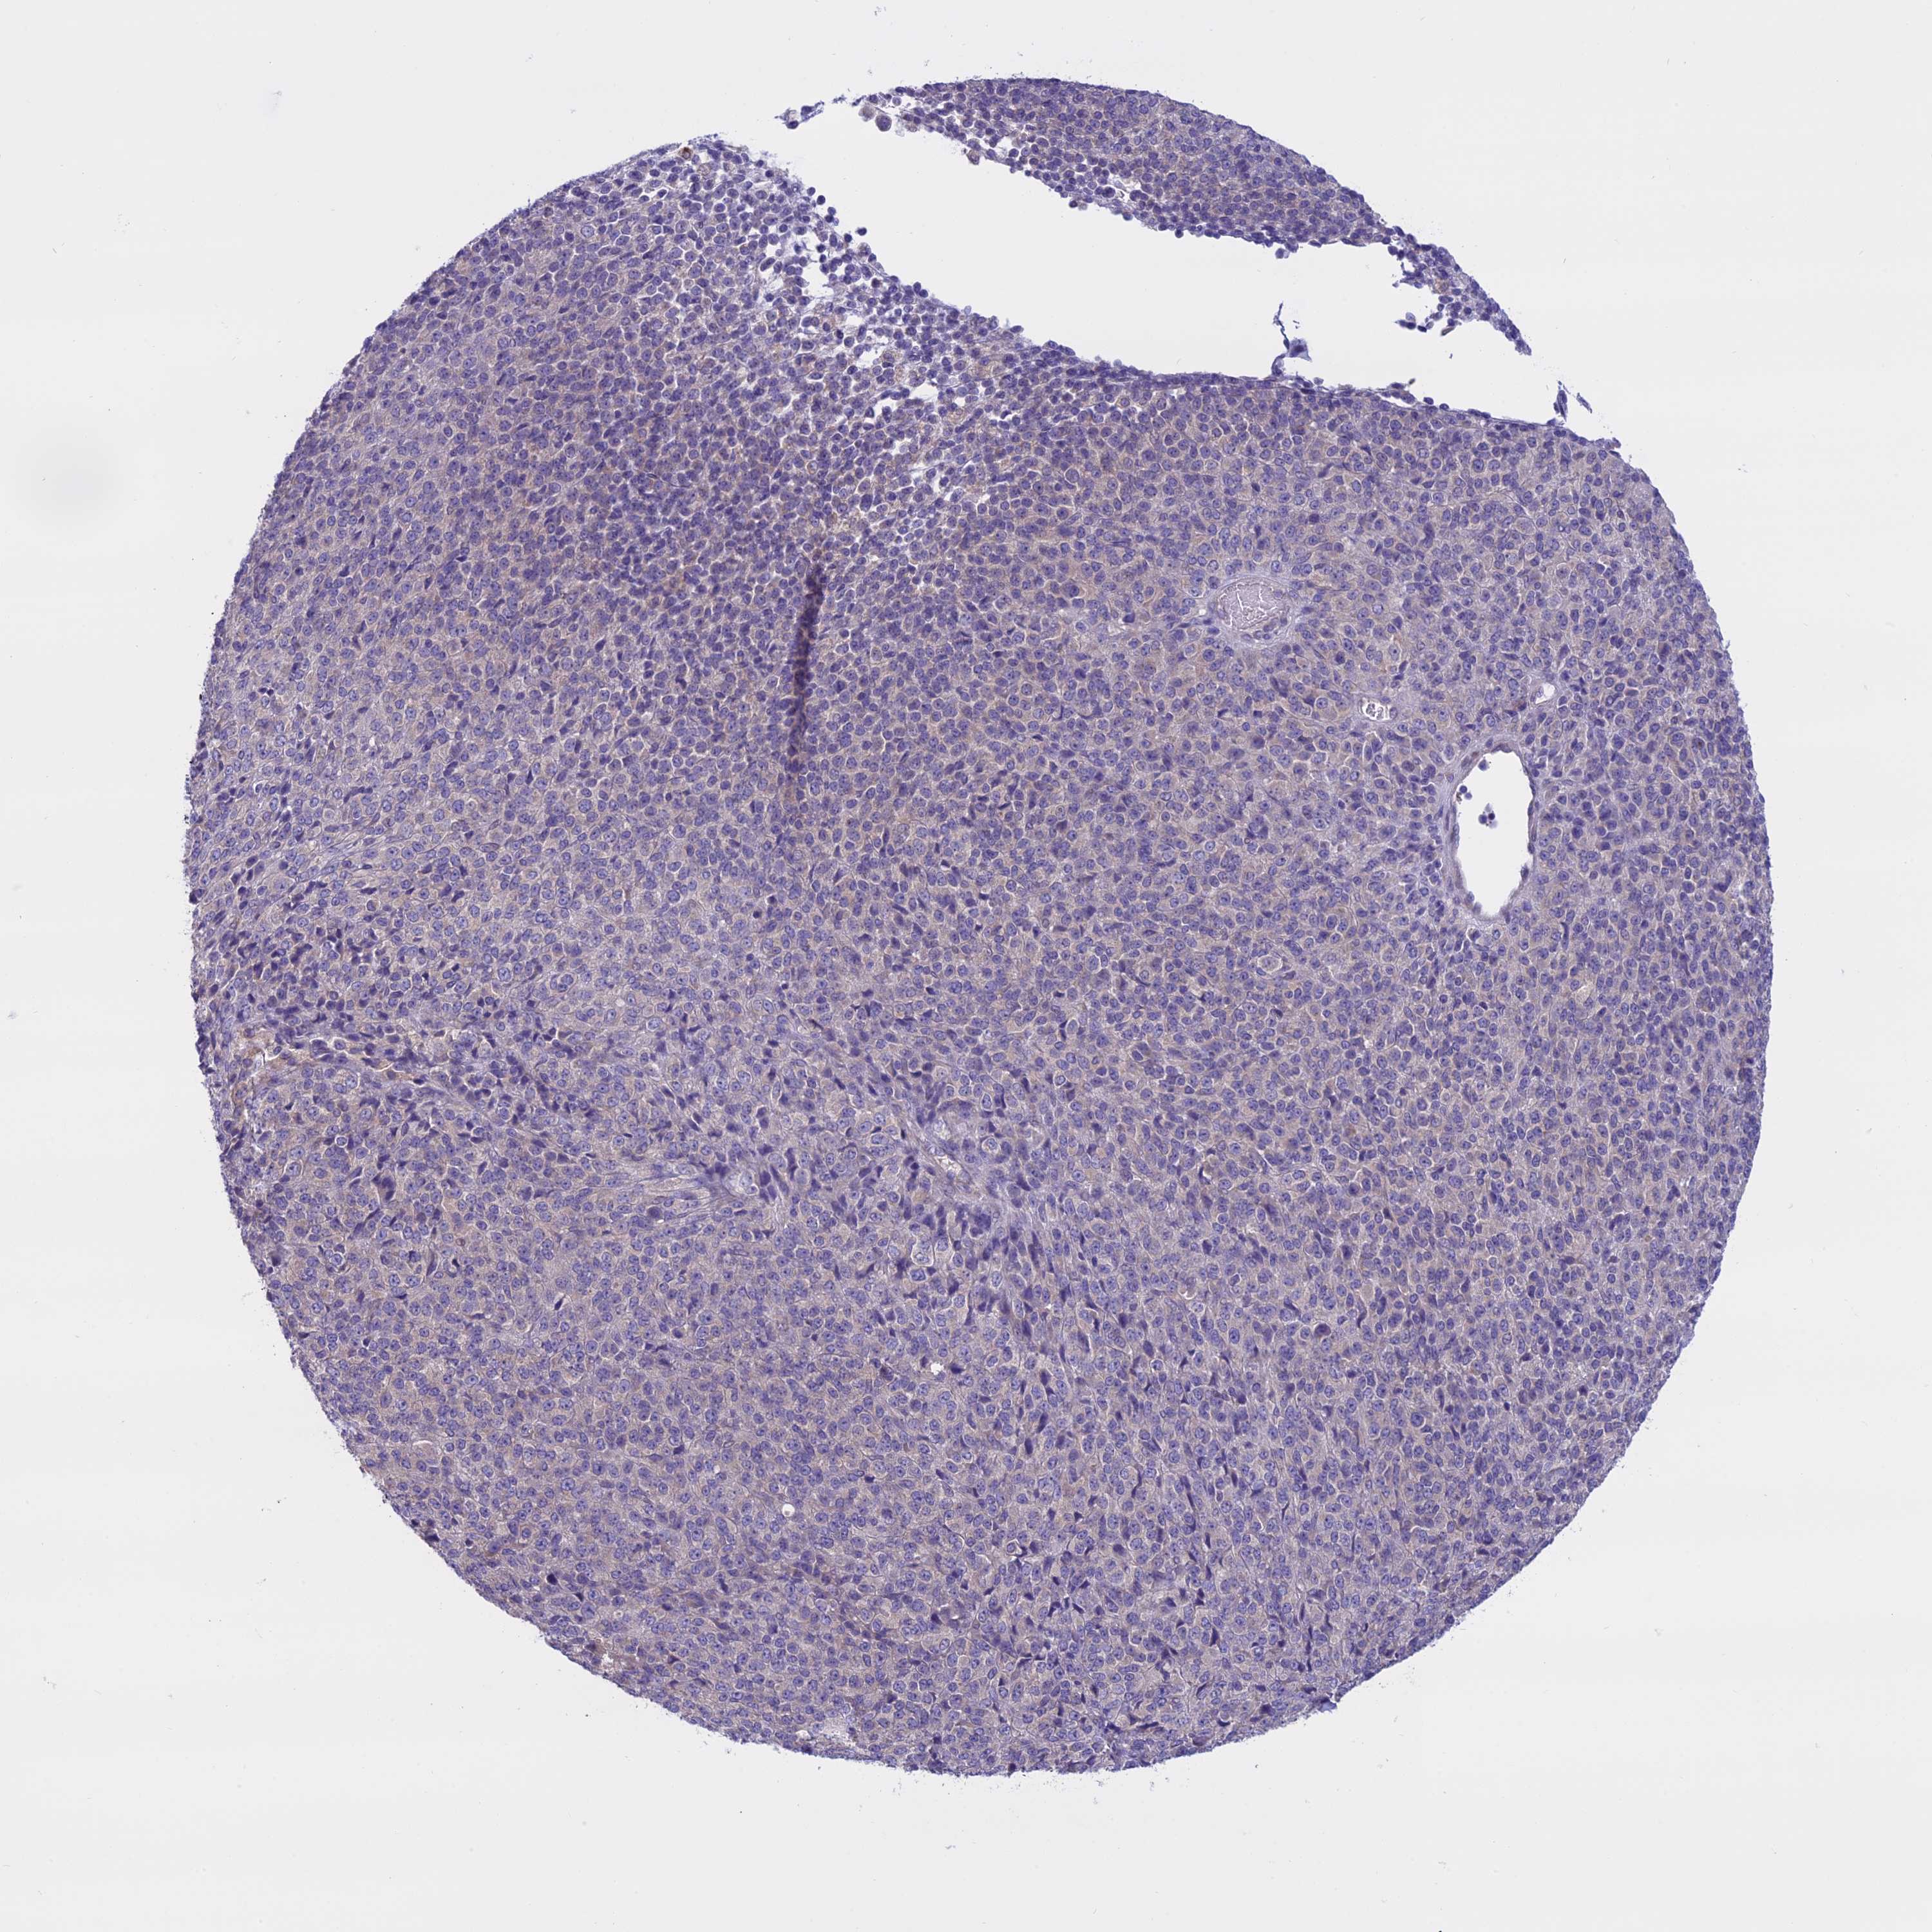

MELANOMA - Protein expressioni

A mouse-over function shows sample information and annotation data. Click on an image to view it in a full screen mode. Samples can be filtered based on level of antibody staining by selecting one or several of the following categories: high, medium, low and not detected. The assay and annotation is described here.

Note that samples used for immunohistochemistry by the Human Protein Atlas do not correspond to samples in the TCGA dataset.

Antibody stainingi

Antibody staining in the annotated cell types in the current human tissue is reported as not detected, low, medium, or high, based on conventional immunohistochemistry profiling in selected tissues. This score is based on the combination of the staining intensity and fraction of stained cells.

Each image is clickable and will lead to virtual microscopy that enables deeper exploration of all samples and also displays staining intensity scores, fraction scores and subcellular localization as well as patient and tissue information for each sample.

Antibody HPA042003

Staining

High

Medium

Low

Not detected

Intensity

Strong

Moderate

Weak

Negative

Quantity

>75%

75%-25%

<25%

None

Location

Nuclear

Cytoplasmic/membranous

Cytoplasmic/membranous,nuclear

Malignant melanoma, NOS

Malignant melanoma, Metastatic site